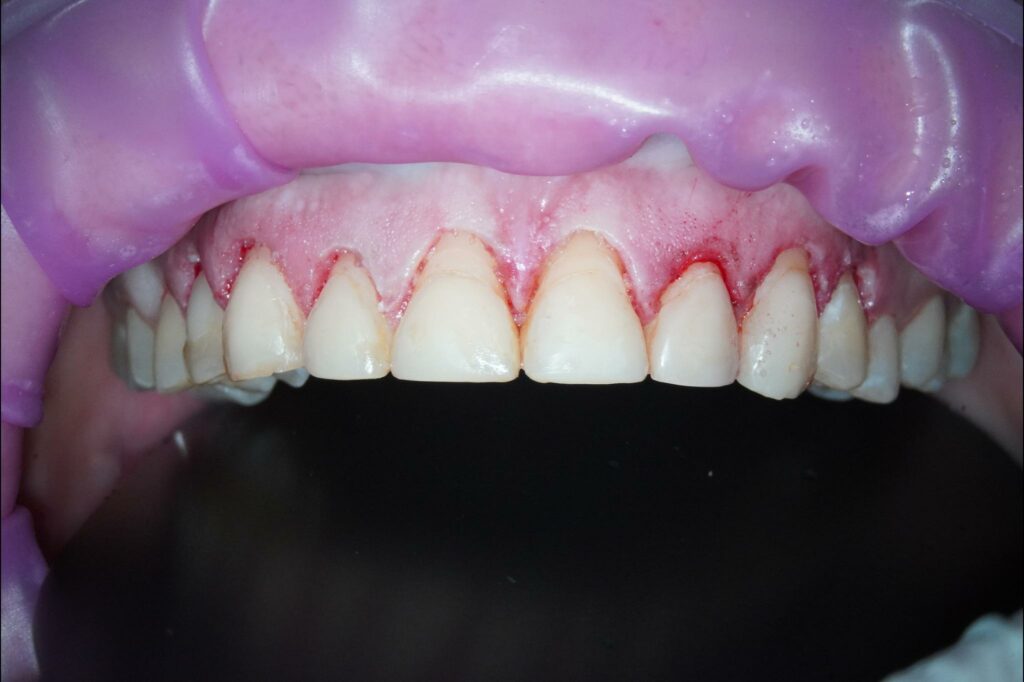

Die Knirscherschiene, die sie zum Schutz

der Zahnsubstanz erhalten hatte, hatte sie kaum getragen. In der aktuellen Situation hatte die Patientin keine Schmerzen, war aber mit dem Erscheinungsbild ihres Lächelns sehr unzufrieden. Ihre allgemeine Anamnese war unauffällig. Der klinische Befund bestätigte, dass die Zähne im Ober- und Unterkiefer, besonders die Frontzähne des Oberkiefers, von starken Abrasionen betroffen waren. Darüber hinaus ergab der klinische Befund bei inkomplettem Zahndurchbruch und ske-lettaler Klasse Il zusätzlich Verfärbungen der Zahnsubstanz und Gingiva-Rezessio-nen (Abb. 2 und 3).